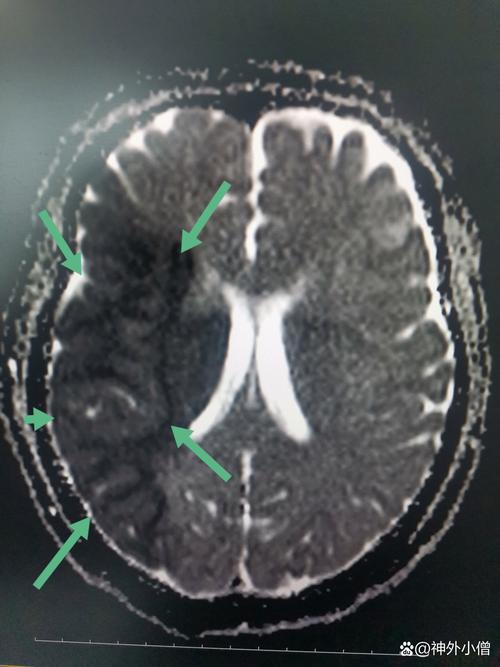

(图片来源网络,侵删)- 这是最重要的一种联系,一些老年人发生大面积脑梗死后,尤其是在脑室周围的区域,可能会影响脑脊液的循环吸收通路。

- 经过一段时间(数月甚至数年),可能发展为一种特殊的脑积水——正常压力脑积水,患者的脑室扩大,但颅内压力在“正常”范围内,但依然会出现步态不稳、认知下降和尿失禁的“三联征”。

- 在这种情况下,脑梗是“因”,而后续的脑积水是“果”,是脑梗的并发症,而不是脑梗的病因。